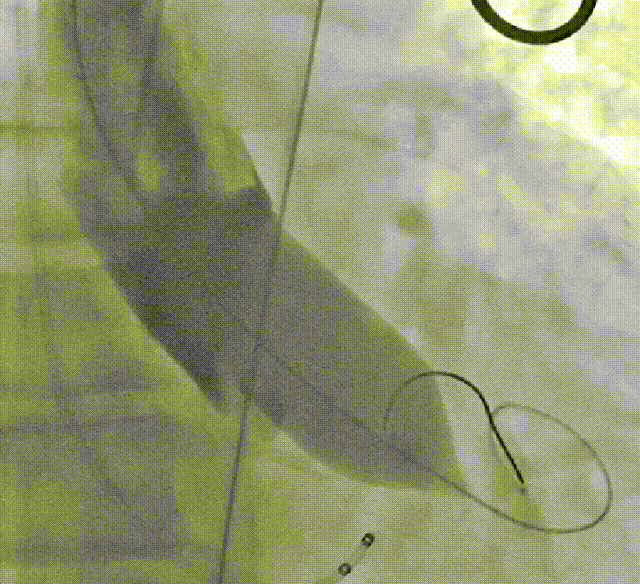

术者采用患者右侧主入路,顺利完成导丝和猪尾跨瓣等准备工作。进Landerquist超硬导丝,采用25mm球囊进行预扩,仔细评估冠脉风险后,决定对冠脉采取保护措施。根据球囊扩张情况,术中决定使用金仕生物的ProStyle预装干瓣TAV32。打开包装后,很迅速的完成了瓣膜和系统植入前的准备。输送过程系统和瓣膜轻松过弓并顺利跨瓣;开始初步释放,然后快速起搏下释放,发现位置略高后进行回收,重新定位后最终成功完成释放。反复造影发现冠脉存在阻塞风险,武汉协和团队按照风险预案在左冠植入4.0*18mm支架进行保护。术后显示左右冠脉血液灌注通畅,术后超声测量峰值流速1.45m/s,峰值压差8mmHg,几乎无瓣周漏。入路闭合顺利,无心脏及血管并发症,手术成功。

支架植入